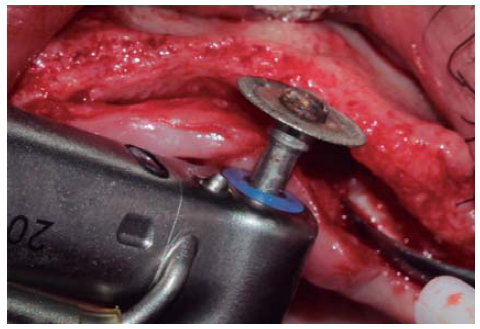

Se realizó una incisión supracrestal a espesor total, elevación del colgajo mucoperióstico exponiendo la tabla ósea hasta 4 mm de la cima de la cresta hacia vestibular y desde ese punto se dividió el colgajo a espesor parcial (Figura 3). Luego se marcaron los puntos de impacto en los sitios designados según la guía quirúrgica para la colocación de los implantes y se iniciaron las perforaciones con una fresa de 1.6 mm de diámetro para determinar el eje y profundidad deseada para los implantes. Luego se procedió a crear un surco a nivel crestal con un disco de diamante rompiendo el hueso cortical para crear el acceso a los escoplos al hueso esponjoso y con éstos se procede a separar las tablas óseas hasta llegar a una profundidad de 5 mm (Figuras 4 y 5). Seguidamente, se continuaron las perforaciones con una fresa de 2.0 mm de diámetro (Figura 6) y se realizó la expansión de la tabla vestibular creando una fractura en tallo verde con los expansores hasta alcanzar el diámetro del lecho óseo suficiente para poder utilizar la última fresa de 3.2 mm de diámetro (Figuras 7 y 8). Posteriormente, se colocaron los implantes a una velocidad de 25 rpm y a un torque de 35 Ncm (Figuras 9 y 10). Seguido de esto, se colocó un injerto óseo bovino particulado (Bonefill® Bionnovation Biomedical, Sao Paulo-Brazil), con la finalidad de preservar la integridad de las tablas óseas vestibulares (Figura 11). Todos estos procedimientos, se realizaron de la misma manera para la colocación de los seis implantes. Finalmente, se suturó con nylon monofilamento 5/0.

Figura 4 Disco de diamante de 0.5 mm de grosor utilizado para crear el surco crestal atravesando el hueso cortical permitiendo el acceso para el cincel óseo.